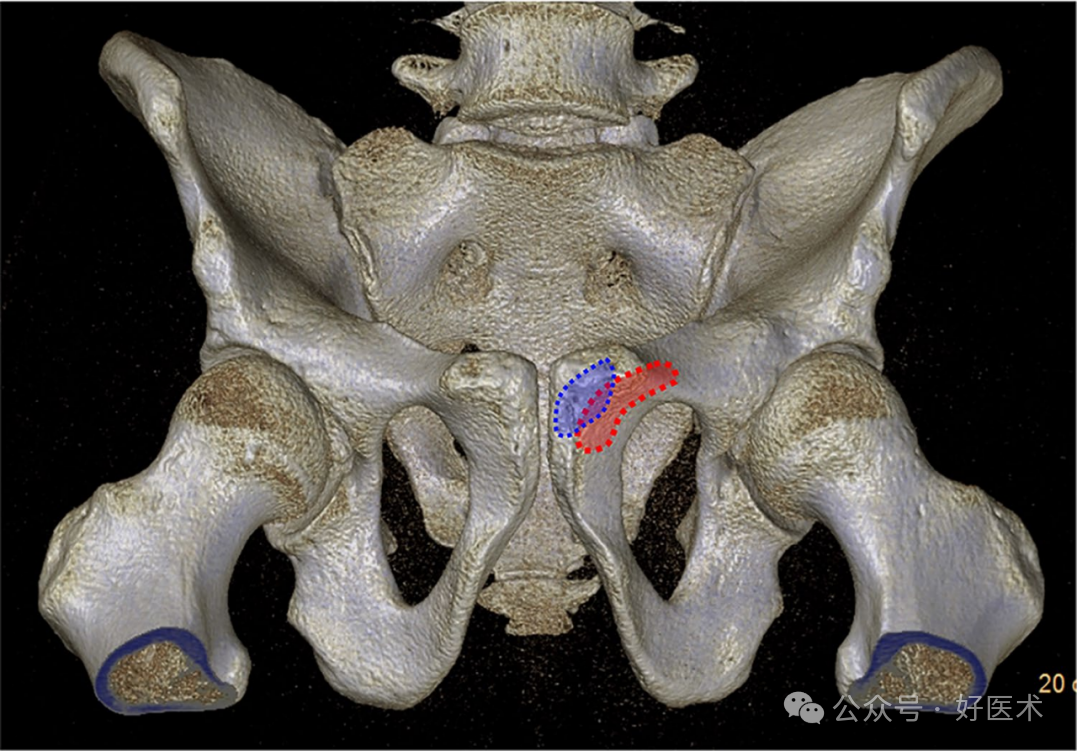

SRC 螺钉适用于耻骨上支中段骨折或位于闭孔上外侧的骨折。耻骨联合中心与进针点的平均距离为27–28mm,而逆行螺钉进针点与耻骨联合中点的距离为18.4±4.8mm。穿刺点与耻骨结节之间的距离为14~17毫米,与耻骨上支上缘的距离为17.8±2.6毫米。Depuis等人未能确定一个普遍可复现的解剖入口。研究报道称存在一个具有性别差异的新月形区域(女性该区域更靠外侧)(见图13)。

适当的骨质起始点位于耻骨结节下方

图 13 逆行螺钉进针点位置。男性(蓝色),女性(红色)。